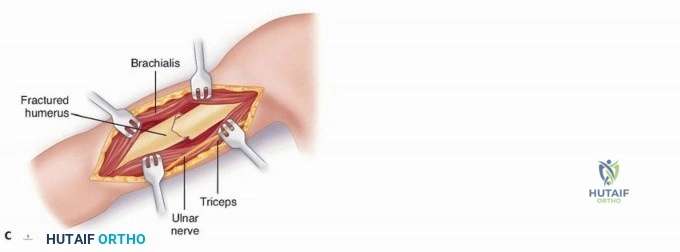

For midshaft fractures, the brachialis muscle is split longitudinally down its midline. Because the medial half is innervated by the musculocutaneous nerve and the lateral half by the radial nerve, this longitudinal split is an internervous plane that preserves the function of both segments. The split is carried down to the periosteum, and the muscle halves are elevated off the anterior humerus. The lateral half of the brachialis acts as a protective muscular cushion between the retractor (and subsequently the plate) and the radial nerve.

For distal third fractures, the exposure must transition to the interval between the brachialis and the brachioradialis. The radial nerve emerges from the posterior compartment by piercing the lateral intermuscular septum and travels distally in the cleft between the brachialis (medially) and the brachioradialis (laterally).

To safely exploit this interval, the fascia between the brachialis and brachioradialis is carefully incised. The radial nerve must be actively identified and protected. It is often easiest to identify the nerve distally where the interval is wider and trace it proximally to where it pierces the septum. Once identified, the nerve is gently mobilized and protected with vessel loops. Retraction of the nerve must be minimal and meticulous to prevent iatrogenic neuropraxia.